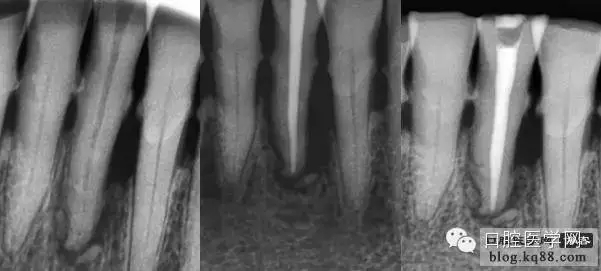

現(xiàn)代的根管充填技術(shù)是通過向預(yù)備好的根管充入牙膠和封閉劑達(dá)到高度的致密性、良好的錐度、精確的長度、所有根管空間(包括分支、側(cè)支、峽部、交通支)的完善封填。

首選錐度等于或稍小于主銼,粗細(xì)型號等同于主銼,比如主銼是8%25#,首選6%25#,如果粗了選擇6%20#,如果細(xì)了選擇6%30#。主尖合適后在尖端3mm要有牽拉感,而且施加合適的力量主尖也不會超出狹窄部。

試好后的主尖經(jīng)X片評價(jià)合適后要放入2.5%的次氯酸鈉中消毒備用,一般3分鐘就可以達(dá)到消毒標(biāo)準(zhǔn),然后充填時(shí)用氣槍吹干,不能用棉球或紗布擦。